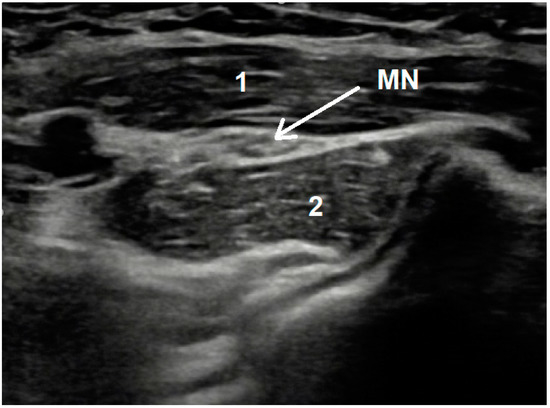

4.2. Lacertus Fibrosus